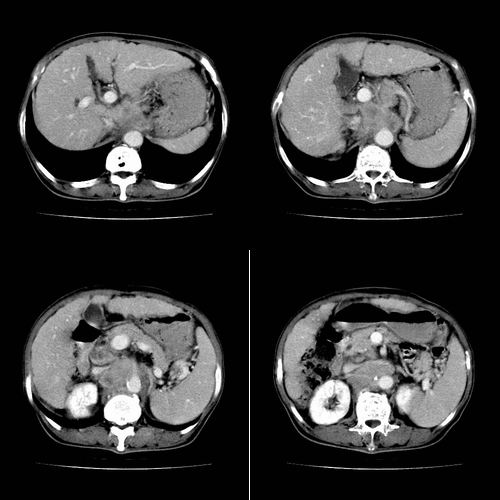

患者 女性 58岁,家族有乙肝病史,(并姊妹中已有3人确诊肝癌,真是不幸!乙肝病毒真是害死人!)近期明显消瘦,乏力,右上腹疼痛.行ct结果非常典型,请诸位老师会诊!

图片非常漂亮!肝内病灶符合较典型肝癌的强化方式,速升速降,其内可见坏死,腹膜后示肿大淋巴结融合成团,包绕腹主动脉、腹腔干动脉、肠系膜动脉。右肾小囊性病灶,未见明显强化。

诊断:肝癌并腹膜后淋巴结转移。

符合右肾囊肿

地一个图是双期扫描`~~~~动脉期肿瘤强化~~静脉期肝实质强化`~肿瘤不强化`~很典型是个肝ca~~

肝脏80%左右有静脉供血~~~所以地一个强化肯定不是肝实质~~~平扫有个低密度的`~结合临床可以肯定

1、肝右叶肝癌,后腹膜淋巴结转移(包绕腹腔干及肠系膜上动脉,推压门静脉、下腔静脉及胰头)

2、肝硬化、脾肿大

3、右肾小囊肿

1、肝硬化,脾肿大

2、肝癌,动静脉瘘(动脉期门静脉内造影剂进入)

3、后腹膜淋巴结转移,下腔静脉推移